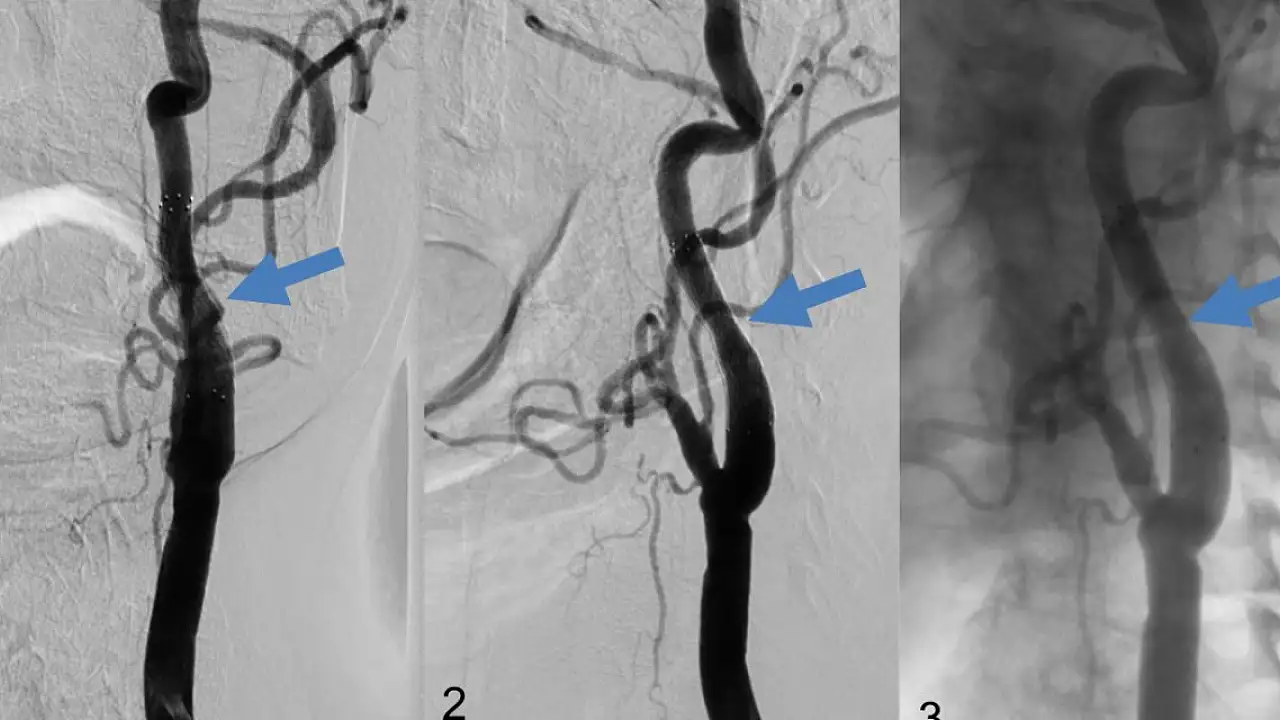

Ameliyatlarla ilgili bilgi veren Köksal, "Nasıl ki tıkalı bir su borusunu ana vanayı kapatmadan temizleyemeyeceğimiz gibi, şah damarı ameliyatlarını da kan akımını durdurmadan yapmak olası değildir. Zaten darlık nedeni ile az kan giden beynimize kan akımını durdurunca hiç kan gitmeyecek ve bu durum ameliyatlarda yaşanabilecek inme riskini arttırabilecektir. Şah damarı ameliyatlarında, özellikle iki taraflı sorun varsa kan akımının devamlılığı çok önemlidir. Ameliyat sırasında kan akımının devamlılığını sağlayan ve şant adı verilen geçici bypaslar, şah damarı ameliyatlarında, özellikle iki taraflı şah damarı darlığı olan hastalarda inme riskini azaltmaktadır. İki taraflı şah damarlarında darlık olan hastalarda beyine giden kan akımını durdurmadan ameliyat yapılması riskleri azaltır" dedi.